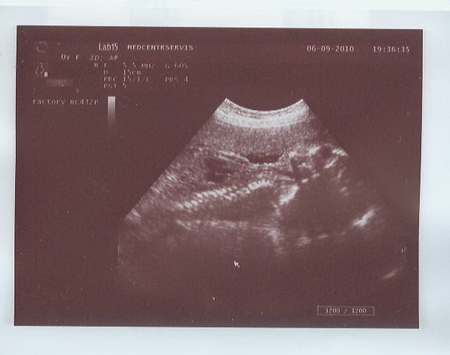

А вот и фото:

1) Вид сбоку - Малыш отвернул немного личико, поэтому и не удалось сделать 3D :(